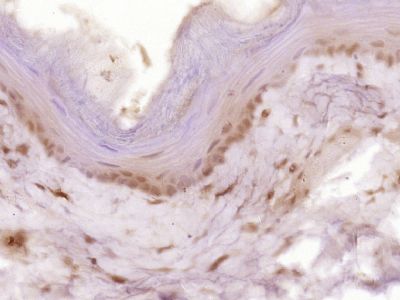

| 产品图片 | ![]() Sample: U937 Cell (Human) Lysate at 30 ug Primary: Anti- Cyclin B1 (bs-0572R) at 1/300 dilution Secondary: IRDye800CW Goat Anti-Rabbit IgG at 1/20000 dilution Predicted band size: 48 kD Observed band size: 50 kD ![]() Sample: U251 Cell (Human) Lysate at 30 ug Primary: Anti- Cyclin B1 (bs-0572R) at 1/300 dilution Secondary: IRDye800CW Goat Anti-Rabbit IgG at 1/20000 dilution Predicted band size: 48 kD Observed band size: 50 kD ![]() Sample: Hela Cell (Human) Lysate at 30 ug Primary: Anti- Cyclin B1 (bs-0572R) at 1/300 dilution Secondary: IRDye800CW Goat Anti-Rabbit IgG at 1/20000 dilution Predicted band size: 48 kD Observed band size: 50 kD ![]() Sample: K562 Cell (Human) Lysate at 30 ug Primary: Anti- Cyclin B1 (bs-0572R) at 1/300 dilution Secondary: IRDye800CW Goat Anti-Rabbit IgG at 1/20000 dilution Predicted band size: 48 kD Observed band size: 50 kD ![]() Paraformaldehyde-fixed, paraffin embedded (Mouse small intestine); Antigen retrieval by boiling in sodium citrate buffer (pH6.0) for 15min; Block endogenous peroxidase by 3% hydrogen peroxide for 20 minutes; Blocking buffer (normal goat serum) at 37°C for 30min; Antibody incubation with (Cyclin B1) Polyclonal Antibody, Unconjugated (bs-0572R) at 1:400 overnight at 4°C, followed by operating according to SP Kit(Rabbit) (sp-0023) instructionsand DAB staining. ![]() Paraformaldehyde-fixed, paraffin embedded (Rat esophageal); Antigen retrieval by boiling in sodium citrate buffer (pH6.0) for 15min; Block endogenous peroxidase by 3% hydrogen peroxide for 20 minutes; Blocking buffer (normal goat serum) at 37°C for 30min; Antibody incubation with (Cyclin B1) Polyclonal Antibody, Unconjugated (bs-0572R) at 1:400 overnight at 4°C, followed by operating according to SP Kit(Rabbit) (sp-0023) instructionsand DAB staining. ![]() Tissue/cell: mouse embryo tissue; 4% Paraformaldehyde-fixed and paraffin-embedded; Antigen retrieval: citrate buffer ( 0.01M, pH 6.0 ), Boiling bathing for 15min; Block endogenous peroxidase by 3% Hydrogen peroxide for 30min; Blocking buffer (normal goat serum,C-0005) at 37℃ for 20 min; Incubation: Anti-Cyclin B1 Polyclonal Antibody, Unconjugated(bs-0572R) 1:500, overnight at 4°C, followed by conjugation to the secondary antibody(SP-0023) and DAB(C-0010) staining ![]() Tissue/cell: human colon carcinoma; 4% Paraformaldehyde-fixed and paraffin-embedded; Antigen retrieval: citrate buffer ( 0.01M, pH 6.0 ), Boiling bathing for 15min; Block endogenous peroxidase by 3% Hydrogen peroxide for 30min; Blocking buffer (normal goat serum,C-0005) at 37℃ for 20 min; Incubation: Anti-Cyclin B1 Polyclonal Antibody, Unconjugated(bs-0572R) 1:200, overnight at 4°C, followed by conjugation to the secondary antibody(SP-0023) and DAB(C-0010) staining ![]() Blank control (blue line): A549 (blue). Primary Antibody (green line): Rabbit Anti-Cyclin B1 antibody(bs-0572R). Dilution: 1μg /10^6 cells; Isotype Control Antibody (orange line): Rabbit IgG . Secondary Antibody (white blue line): F(ab’)2 fragment goat anti-rabbit IgG-FITC. Dilution: 1μg /test. Protocol The cells were fixed with 2% paraformaldehyde (10 min) and then permeabilized with 0.1% PBS-Tween for 20 min at room temperature.Cells stained with Primary Antibody for 30 min at room temperature. The cells were then incubated in 1 X PBS/2%BSA/10% goat serum to block non-specific protein-protein interactions followed by the antibody for 15 min at room temperature. The secondary antibody used for 40 min at room temperature. Acquisition of 20,000 events was performed. ![]() Cell: Hela Concentration:1:100 Host/Isotype:Rabbit/IgG Flow cytometric analysis of primary antibody (Cat#: bs-0572R) on Hela(green) compared with isotype control in the absence of primary antibody (blue) followed by Alexa Fluor 488-conjugated goat anti-rabbit IgG(H+L) secondary antibody . |